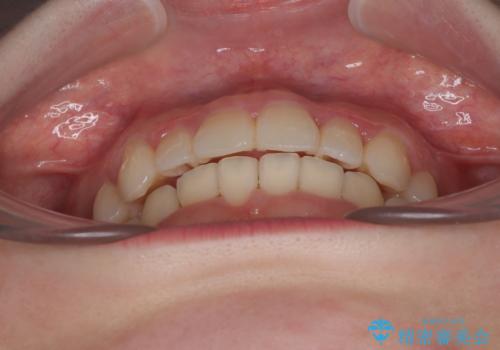

飛び出した前歯を引っ込める ワイヤー装置の非抜歯矯正

- 上下前歯のデコボコを気にして来院された患者様です。

見た目や咬み合わせに違和感がないとのことで、癒着歯の無理な移動は試みずに治療を終えることとしました。